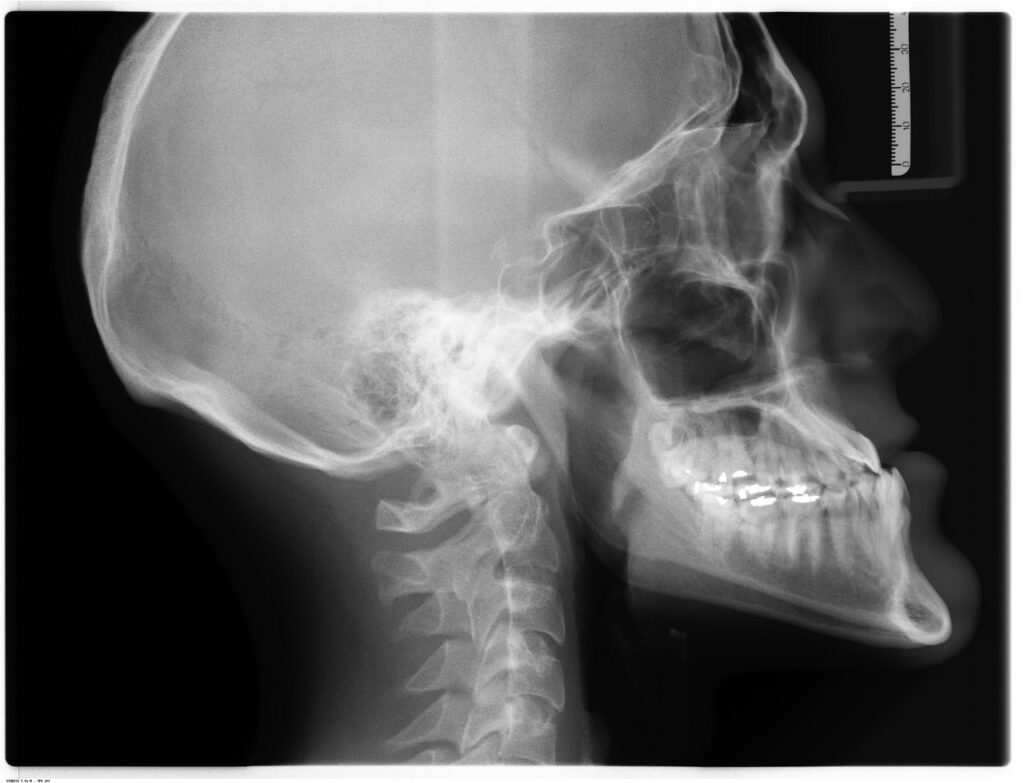

X-rays are one of the most common types of imaging. They use electromagnetic radiation to capture images of bones and are useful in diagnosing broken bones or joint problems. CT scans are similar to X-rays; however, they capture images from different angles to create a more detailed image.